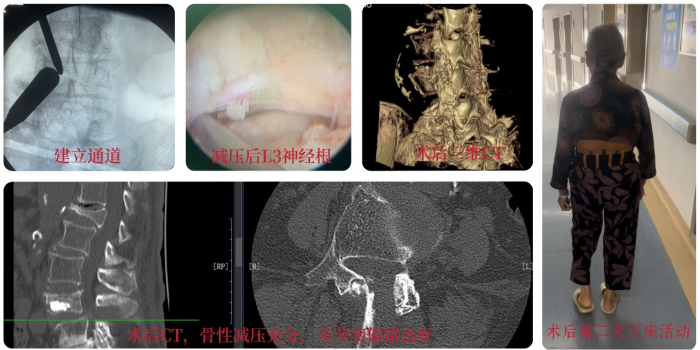

经过周密的术前准备,肖强团队为患者实施了微创手术,手术顺利,总出血量不超过50ml。麻醉清醒后黄奶奶的腰痛、腿痛症状均明显改善,第二天就能下床自如行走了;复查CT影像提示责任神经根(L3)得到了充分减压,而脊柱的稳定结构得到了很好保留,真正实现了微创、精准治疗。目前,黄奶奶已顺利出院,随访情况良好。